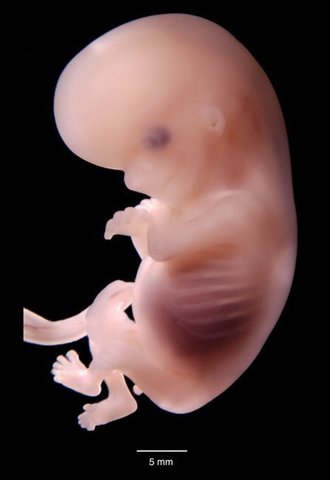

• La neurogénesis

el embrión se convierte en feto. En esta etapa, los tejidos y los órganos formados en la fase embrionaria maduran .La cola del embrión empieza a caer. El corazón late y el esqueleto adquiere forma. El bebé crecerá más del doble esta semana: medirá alrededor de 1 centímetro.La neurogénesis es un proceso de división celular extremadamente rápida que produce neuronas.